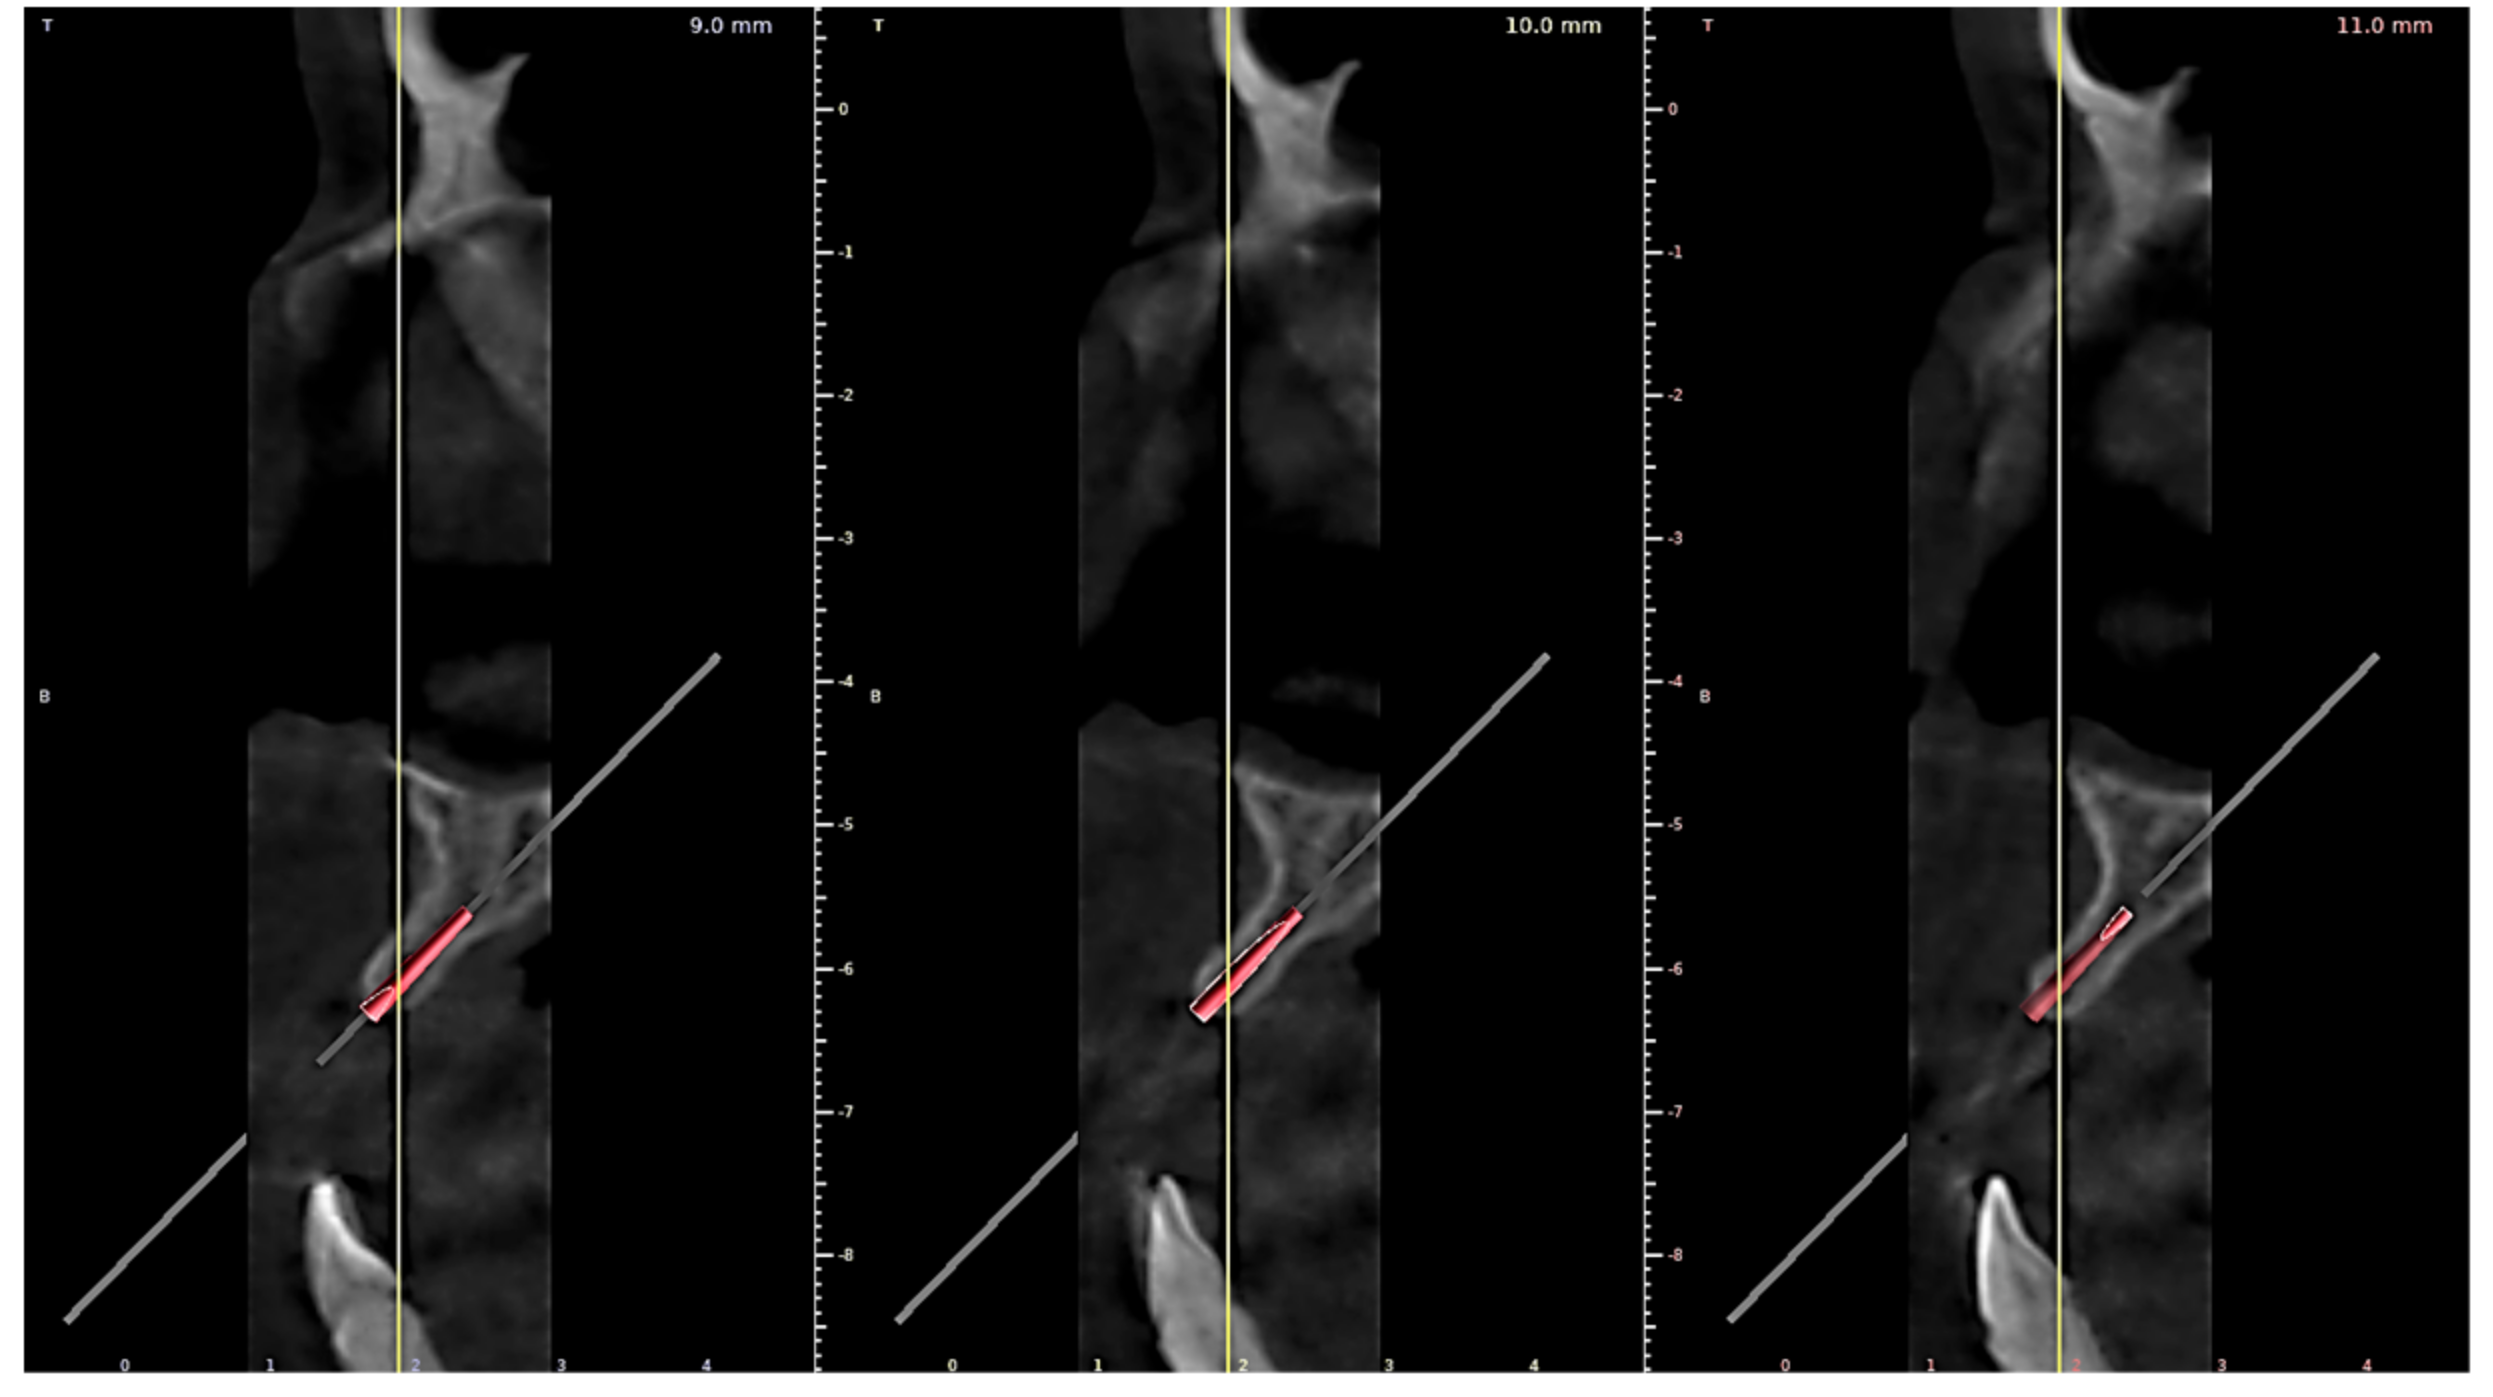

2.2. Computer Aided TAD Insertion Guide Design

2.3. Finite Element Analysis of Individualized TAD Insertion Guide